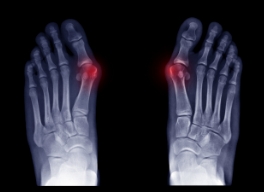

外反母趾(がいはんぼし)とは、足の親指が小指側に向かって「くの字」に変形し、付け根の関節が内側に突出する疾患です。変形に伴って靴との摩擦が生じ、炎症や痛みを引き起こすことがあります。

外反母趾の変形は「第1中足趾節関節」(親指の付け根の関節)の歪みによって起こります。親指が外側に向かって曲がることで、付け根部分が内側に出っ張り、靴などに当たって炎症を起こしやすくなります。

医学的には親指と中足骨がなす角度(外反母趾角)で診断され、15度以上で外反母趾とされます。

- 軽度(15〜25度)

- 中等度(25〜35度)

- 重度(35度以上)

症状は徐々に進行し重度になると親指が他の指に重なったり、指の脱臼や変形を伴ったりすることもあります。